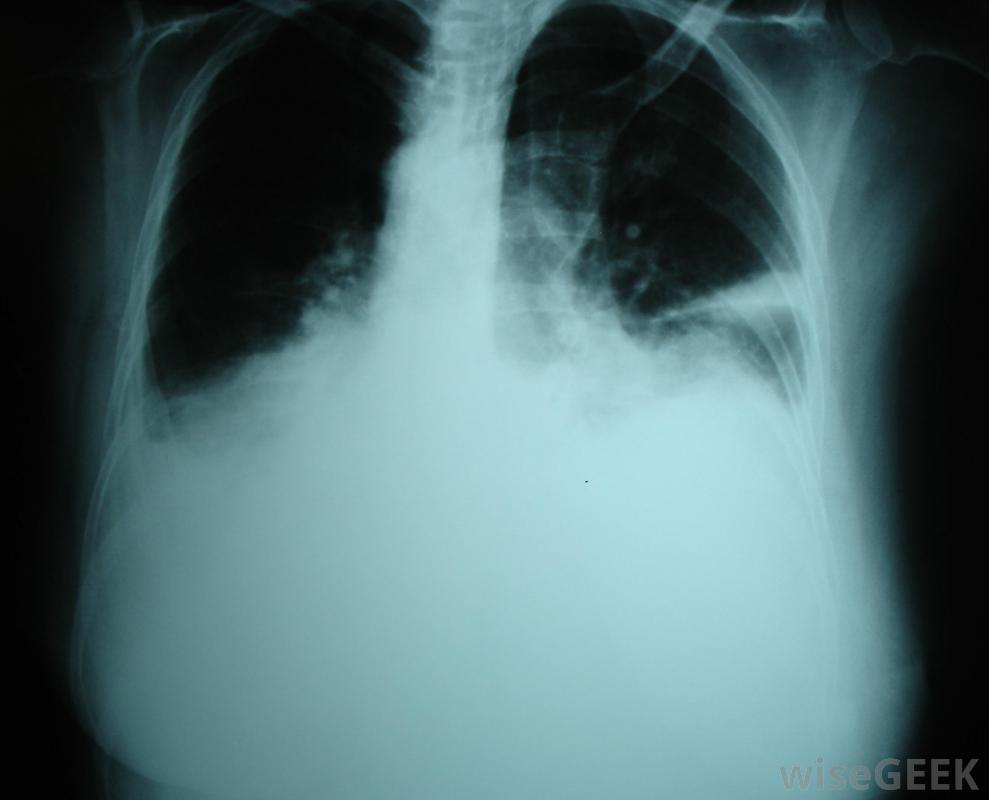

胸腔積液可能是fontan手術的并發癥。

Fontan手術通常在嬰兒兩歲后進行,因為嬰兒由于血管阻力高或血液通過循環系統需要大量的工作而無法忍受手術。并發癥可能包括感染、胸腔積液或積液肺部和心房顫動。這些并發癥可能需要短期或長期使用藥物、胸腔導管和手術。在某些情況下,Fontan手術可能無法充分改善患者的健康和生活質量,患者可能需要心臟移植。然而,對于許多患者來說,手術使孩子能夠正常發育,過上正常、健康的生活。